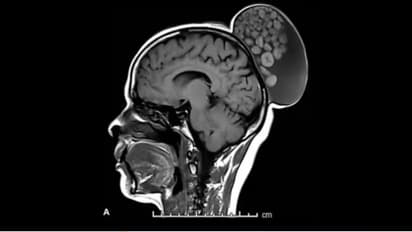

बेंगलुरु में डॉक्टरों ने हाल ही में एक महिला का अनोखा ऑपरेशन किया है। जिसके सिर पर कंचे की बोरी जैसी उभरी हुई गांठ थी। श्रीसत्य साईं इंस्टीट्यूट ऑफ हायर मेडिकल साइंसेज ने रेडियोलॉजी पत्रिका में इस असामान्य ऑपरेशन के बारे में विस्तार से जानकारी दी है। 52 वर्षीय महिला बचपन से ही सिर पर सूजन के साथ जी रही थी लेकिन अब तक उसने कभी इसकी जांच भी नहीं कराई थी। इस सूजन में दर्द नहीं होता था और यह करीब 6 इंच लंबी, 4 इंच चौड़ी थी।

एमआरआई स्कैन से मिली डॉक्टरों की इसकी जानकारी

डॉक्टर्स ने जब इसकी जांच की तो एमआरआई स्कैन से पता चला कि यह गांठ उसके सिर के पीछे मांसल भाग में बालों के जूड़े जैसा बन गया था। इसको हटाने के लिए की गई सर्जरी के दौरान डॉक्टरों ने पाया कि यह तरल पदार्थ, बाल, वसायुक्त अणुओं और मोटे बाहरी किनारों के साथ केराटिन की बॉल्स से भरा हुआ था, जो अलग-अलग आकार के थे। जानकारी के लिए बता दें कि केराटिन एक तरह का प्रोटीन होता है जो बालों, नाखूनों और स्किन की बाहरी पर्त का आधार बनता है। महिला में मिले इस चीज को डर्मोइट सिस्ट कहते हैं। यह भ्रूण कोशिकाओं से ही बनते हैं और यह बाल, दांत या तंत्रिकाएं बना सकते हैं। ये अक्सर सिर और गर्दन में दिखते हैं। यह अंडाशय और शरीर के ऊपरी हिस्से में भी पाया जाता है।